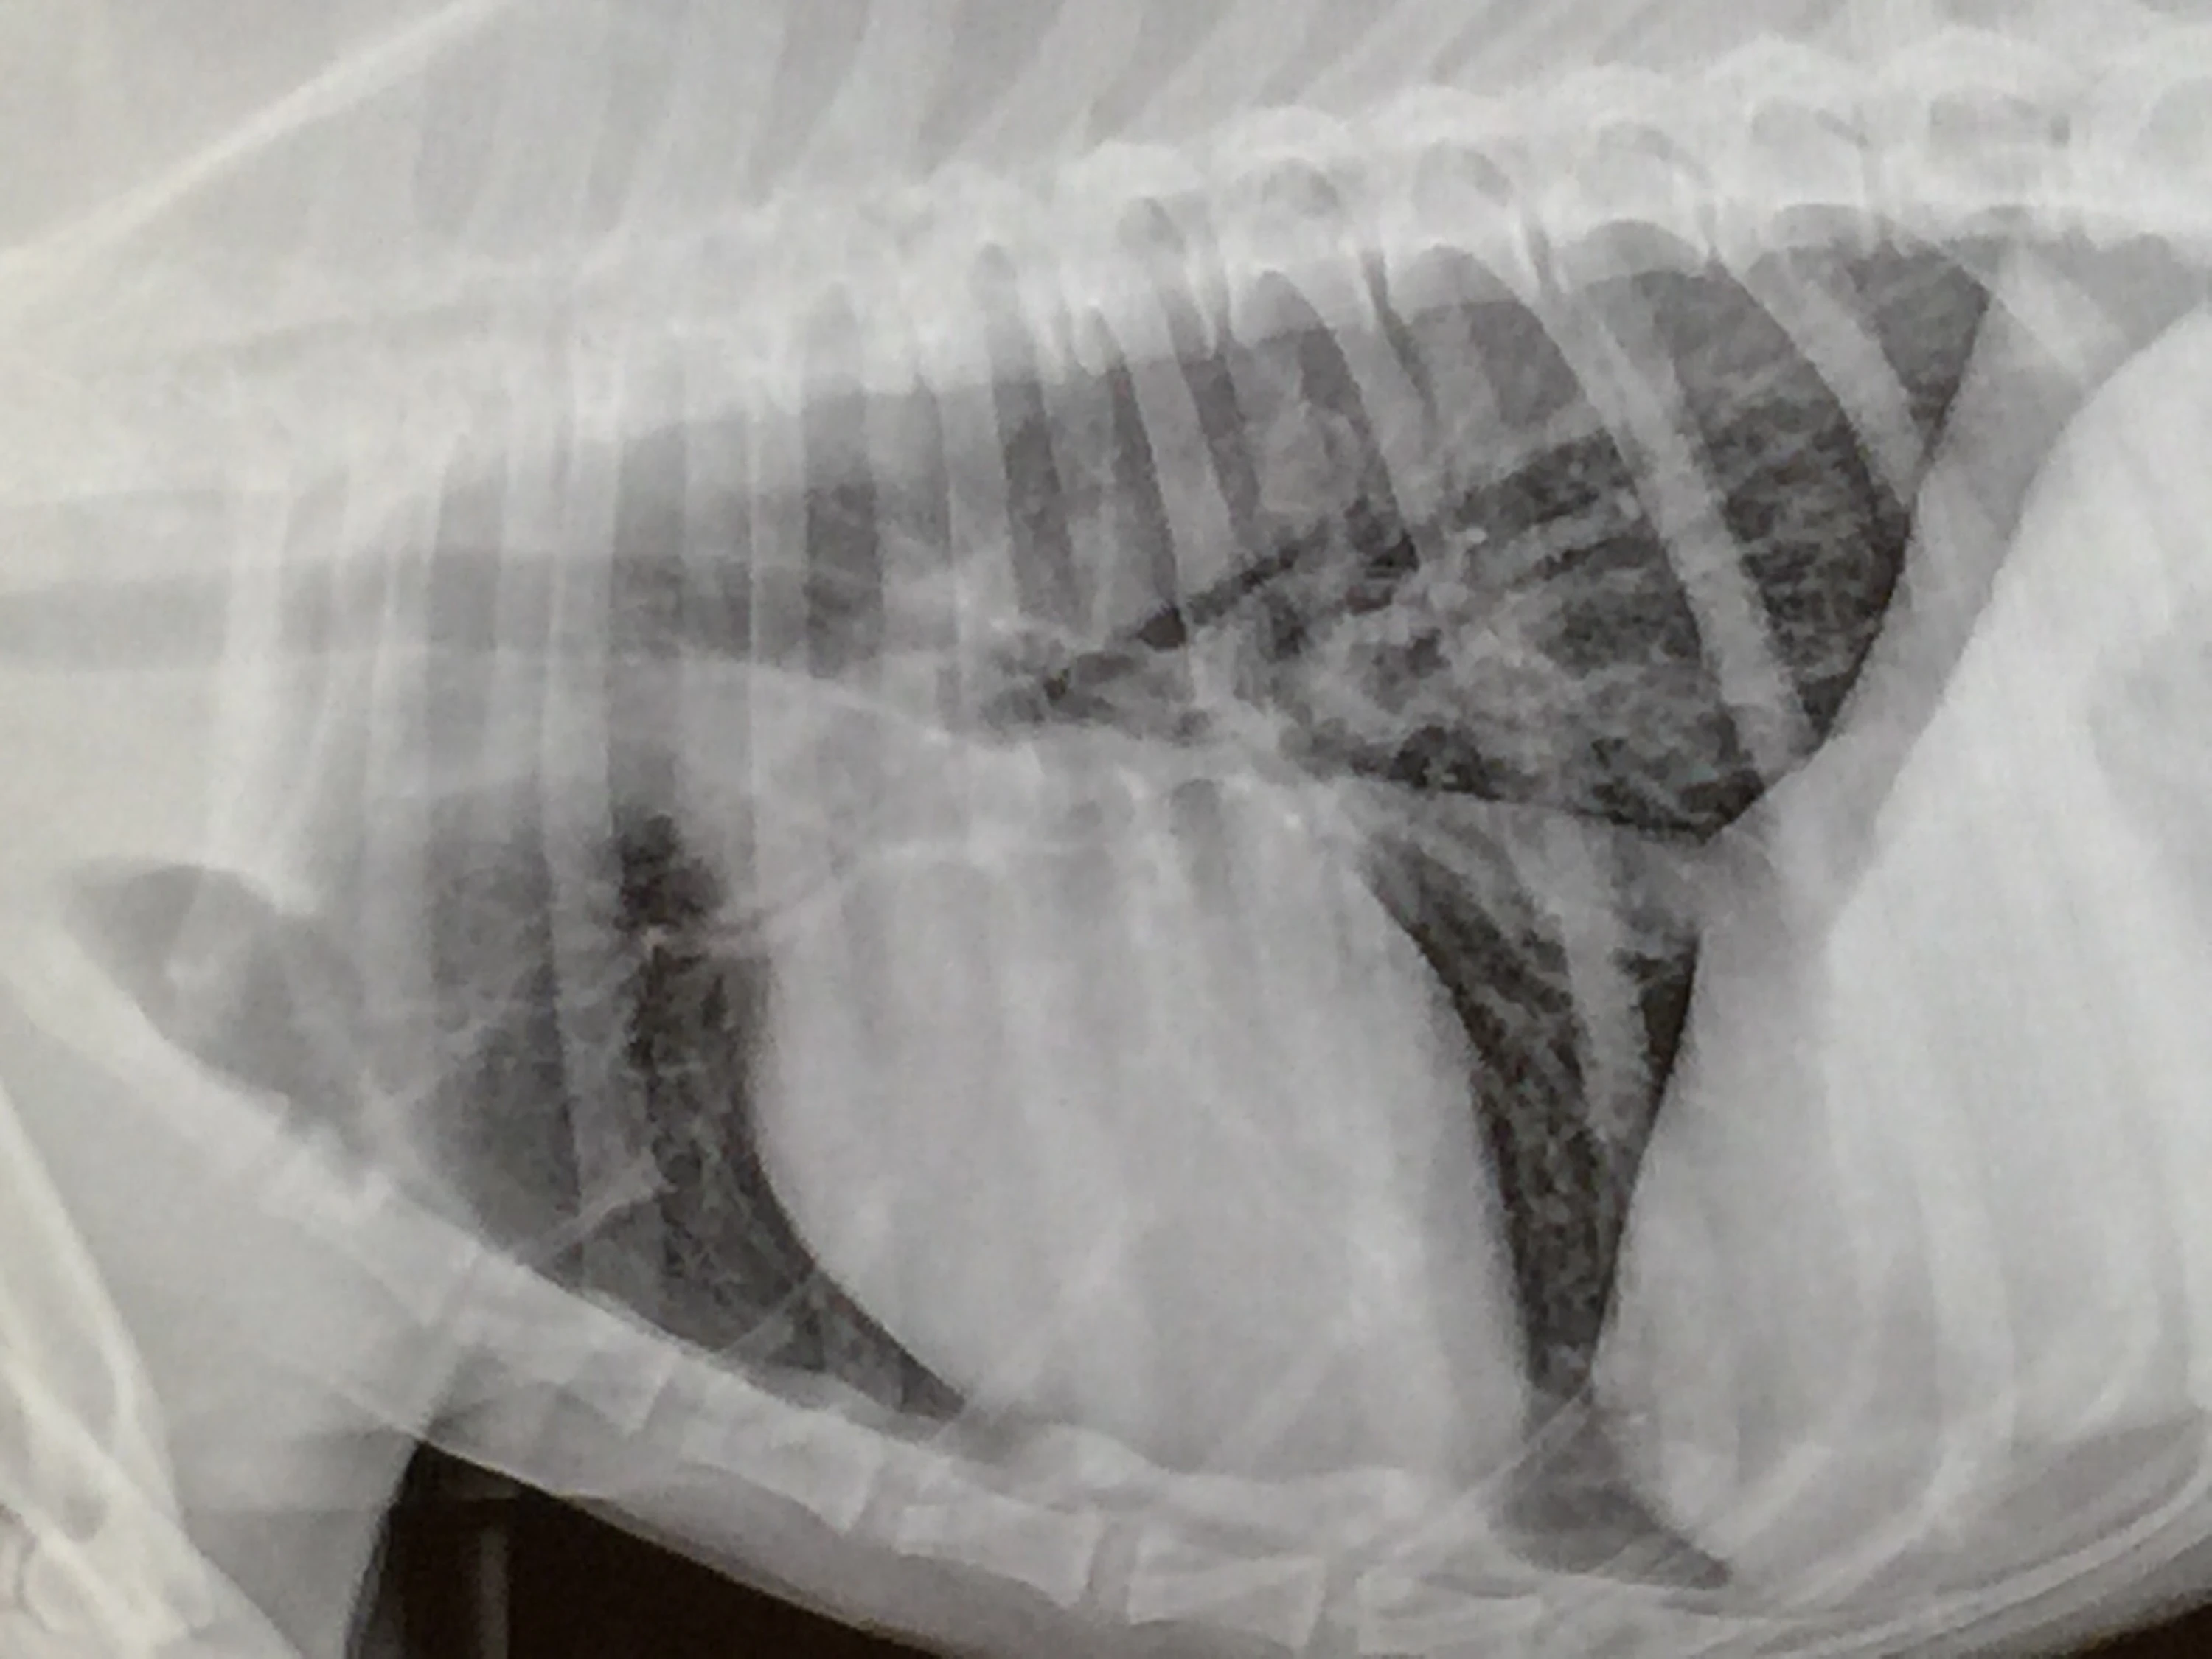

Bromont's Chest X-Rays are Clear. -Yeah

So far so good. I was worried about this more than what the pathology report will be. We’re just hanging in Fort Collins for a few hours so we can take him home after.

Trent showing us Bromont’s X-Rays.